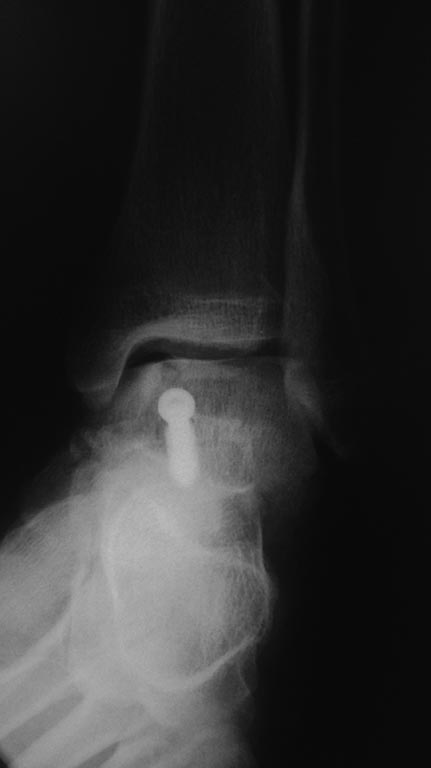

Во вложении всего два примера нормальных взаимоотношений в подтаранном суставе. Постарался подобрать похожие на Вашу проекции. На всех снимках выделена область, где суставные поверхности таранной и пяточной костей всегда должны быть параллельны. В Вашем случае эти линии пересекаются. Подвывих очевиден.

Два дня был без доступа к интернету. Во вложении недавний случай остеосинтеза оскольчатого переломовывиха таранной кости. Методика классическая. С анатомической репозицией и стабильной фиксацией. Без гипса после операции.